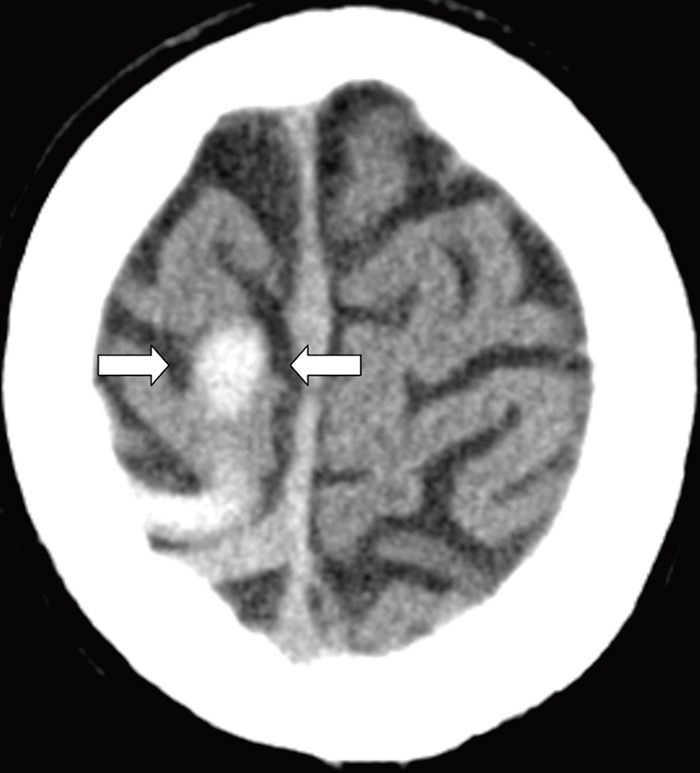

En tidligere frisk kvinne i 40-årsalderen hadde fra dagen før innleggelsen morgenhodepine og oppkast. Hun var ikke-røyker og brukte ingen medisiner eller hormoner. Innleggelsesdagen utviklet hun akutt parese i venstre ansiktshalvdel, venstresidig armparese og dysartri. Hun hadde forbigående rykninger i venstre ansiktshalvdel. Cerebral CT utført ved lokalsykehuset viste en høyattenuerende lesjon i høyre temporoparietallapp (bilde kun på nett). D-dimer var 0,8 mg/l (normalt < 0,4). Man mistenkte vaskulær hendelse i høyre hemisfære. Cerebral MR-venografi ved universitetssykehuset dagen etter viste en intraluminal venøs fyllingsdefekt svarende til høyre vena Trolard (bildet til venstre). Diffusjonsvektet cerebral MR viste en blanding av vasogent og cytotoksisk ødem temporoparietalt, typisk for venøst infarkt (bildet til høyre). Testing av forstyrrelser i trombose-koagulasjonssystemet viste aktivert protein C-resistens 0,66 (normalt 0,85 – 1,15). Pasienten fikk antikoagulasjonsbehandling og seks dager etter initiering av antikoagulasjon var ny cerebral MR-venografi normalisert. Hun ble utskrevet uten sekvele.